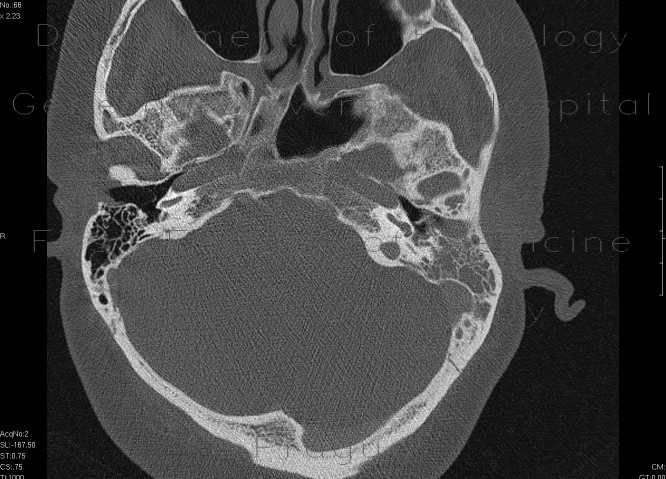

Acute Mastoiditis - Diagnostic Imaging

Bilateral chronic otitis media and mastoiditis with external wall breakthrough and an adjacent subperiosteal inflammatory process or abscess on the left. An immediate left complete corticomastoidectomy for acute suppurative coalescent mastoiditis was performed. ... Return Doc